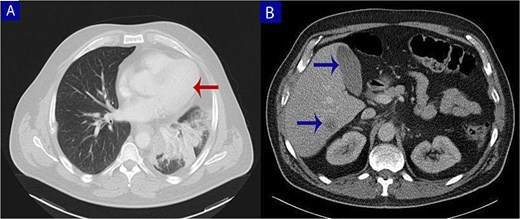

Contrast-enhanced computed tomography (CT) of the chest, abdomen, and pelvis. (A) Axial chest CT shows a lobulated mass (arrow) with heterogeneous enhancement centered at the left pulmonary hilum, invading adjacent bronchial and vascular structures. (B) Abdominal CT reveals multiple hypodense lesions in the liver (arrows), consistent with hepatic metastases.

Radiologically, the largest mass was centered in the left upper pulmonary hilum, while the hepatic lesions were smaller and more scattered—consistent with secondary liver metastases rather than a primary hepatic tumor.